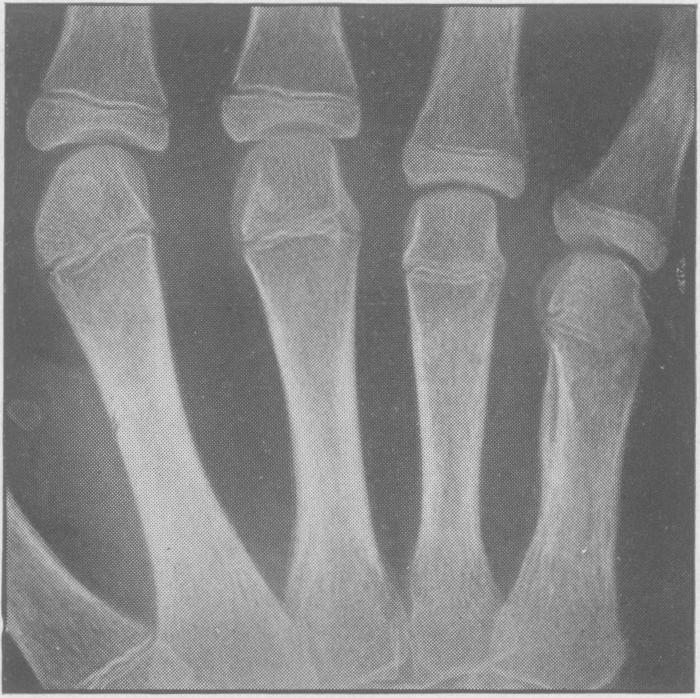

Juvenile rheumatoid arthritis (Still's disease).